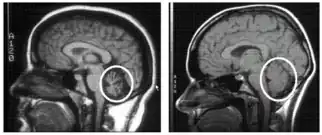

| Cerebellum (labeled bottom right) of the human brain. It is located above the brain stem, posterior to the brain. | |

To select an appropriate and accurate diagnostic test for cerebellar degeneration, it is crucial that a range of factors specific to each patient are taken into consideration. These include; the patient's age, acuity of their signs and symptoms, associated neurological conditions, and family history of hereditary forms of cerebellar degeneration.[3] A diagnosis for cerebellar degeneration is regarded after any of the aforementioned signs and symptoms surface. For genetically classified forms of cerebellar degeneration, genetic testing can be carried out in order to confirm or deny the diagnosis, where this form of testing is only possible if the gene responsible for the cause of the condition is recognised.[24] In saying this, for most conditions the genetic cause of cerebellar degeneration is unidentified, hence these patients cannot proceed with genetic testing.[1] In cases where cerebellar degeneration is acquired, a diagnosis can be established using imaging methods such as computerised tomography (CT scans) and magnetic resonance imaging (MRI), necessary to detect brain abnormalities in patients with cerebellar degeneration.[25]